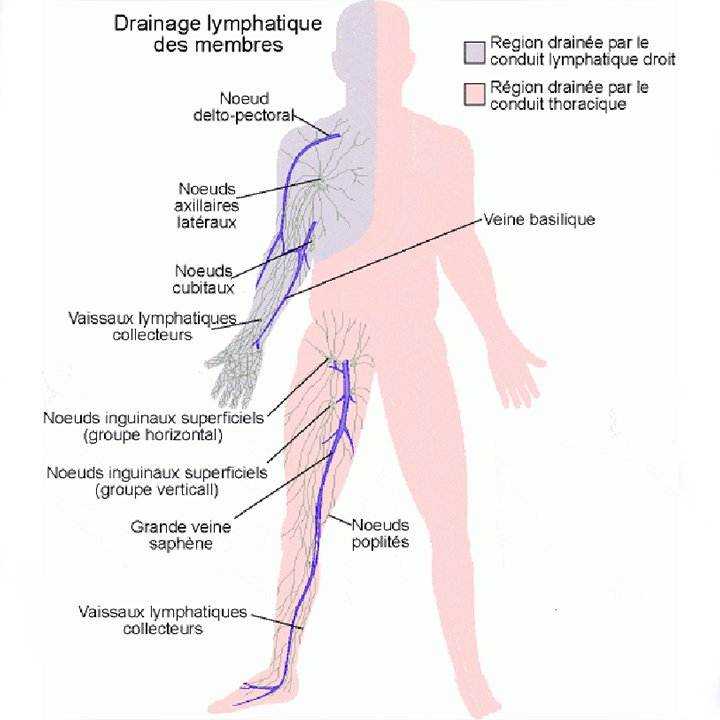

Lymphoedème

Lire

Le drainage

Le drainage lymphatique est une technique pour traiter les œdèmes, les lourdeurs de jambes

Le Lymphoedeme

Le lymphœdème est un gonflement chronique dû à une accumulation de lymphe dans les tissus. Il peut survenir après une chirurgie, une radiothérapie, un traumatisme ou être d’origine congénitale.